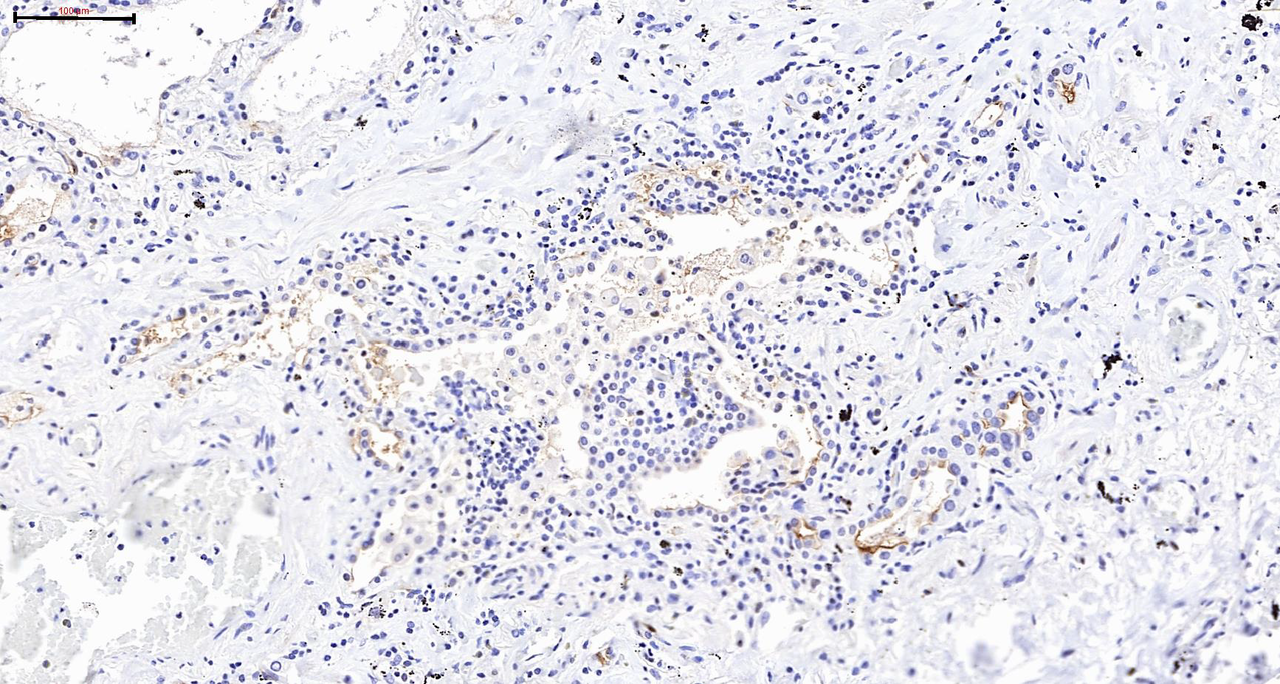

The alveolus is the functional unit of the lung where gas exchange occurs. Alveolar type 2 (AT2) cells produce surfactant which reduces surface tension in the lung and allows it to remain expanded and they also are a stem cell population that replenishes damaged alveolar type 1 (AT1) cells. AT1 cells form a very thin layer in close approximation with the capillary endothelium to allow diffusion of oxygen and carbon dioxide. A viral infection can trigger a severe inflammatory condition called acute respiratory distress syndrome (ARDS) where AT1 and AT2 cells are damaged leading to the alveolus filling with fluid and inflammatory cells; thus, preventing the alveolus from participating in gas exchange. Many of the patients with COVID-19 who were hospitalized in an ICU or died developed ARDS in response to their infection. We found that in CLD patients, the AT2 cells especially showed altered expression of genes in signaling pathways essential for viral replication and the immune response to viral infection. The immune cells essential for responding to and controlling a viral infection but also for propagating the damage that leads to ARDS were also abnormal in CLD patients: at baseline these CLD immune cells expressed markers of exhaustion and higher levels of cytotoxic genes (Figure 1). In conclusion, we observed broad changes and dysregulation in the gene expression profile related to viral infection and host response in CLD patients, suggesting that CLD patients may respond completely differently to viral infection, including SARS-CoV2, compared to individuals without lung disease.

Figure 1. Model of alterations in the diseased lung related to SARS-CoV2 pathogenesis.